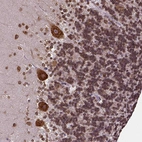

Immunohistochemical staining of human cerebral cortex shows strong cytoplasmic positivity in neurons.